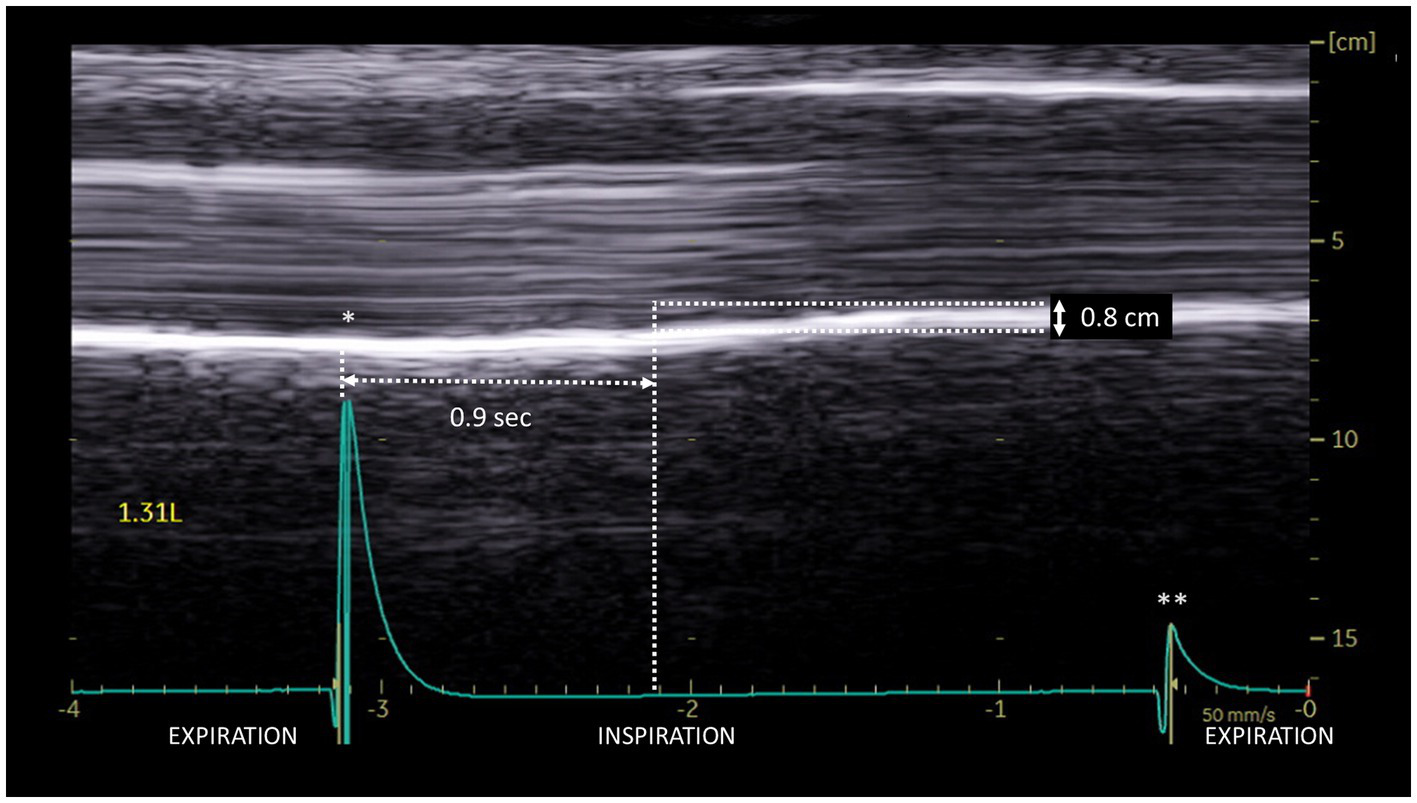

Another rare profile can be observed as a delayed-motion picture (Figure 5). In some subjects, during quiet breathing, a normal (cranio-caudal) excursion was seen but delayed from the onset of inspiration. This profile can also be recorded during deep inspiration (in 14% of patients). The time between the beginning of the inspiration and the caudal excursion was on average 0.4 s.

Figure 5

Delayed cranio-caudal excursion on the paralyzed side during inspiration (volume = 1.31 L): excursion (0.8 cm) occurred after a period of no movement at the beginning of inspiration (here 0.9 s). *Beginning of inspiration. **Beginning of expiration.